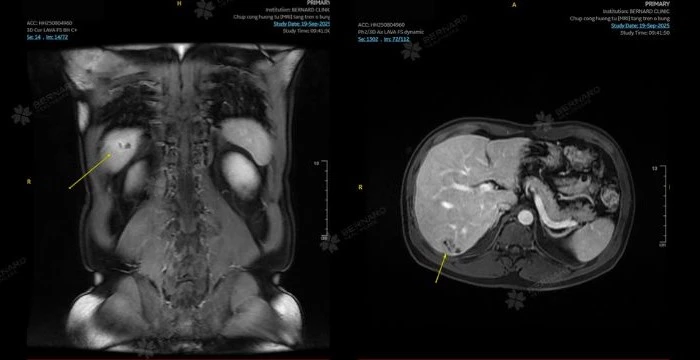

Để làm rõ bản chất tổn thương, bệnh nhân được chỉ định chụp MRI bụng có tiêm thuốc tương phản. Kết quả MRI cho thấy thêm một số nang gan nhỏ ở các phân thùy IV, VI và VII.

Riêng tổn thương tại phân thùy VI được xác định rõ hơn với kích thước khoảng 15×25 mm, bờ mờ, tín hiệu thấp trên T1W, cao không đồng nhất trên T2W và xuất hiện cấu trúc dạng ống ngoằn ngoèo trong lòng tổn thương.

Hình ảnh này gợi ý mạnh đến nhiễm Fasciola hepatica (sán lá gan lớn) – một loại ký sinh trùng có thể gây tổn thương gan kéo dài. Tổn thương không hạn chế khuếch tán và bắt thuốc kiểu viền muộn, khiến khả năng u gan trở nên ít phù hợp hơn. Sự đồng thuận giữa hình ảnh học và xét nghiệm máu giúp bác sĩ hướng nhiều đến chẩn đoán viêm gan do ký sinh trùng.